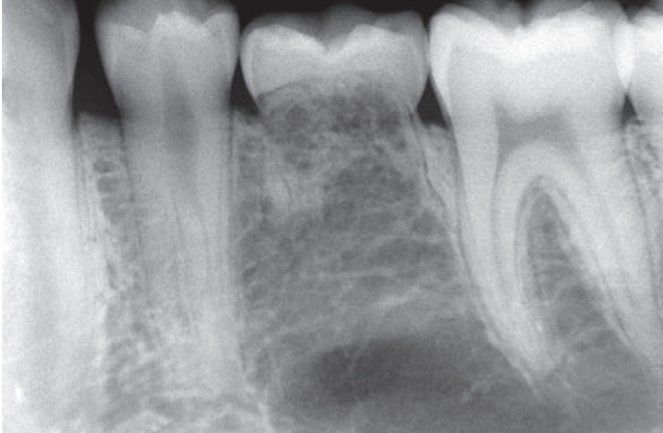

Anodontia of a permanent second premolar with ankylosis of an erupted primary molar.